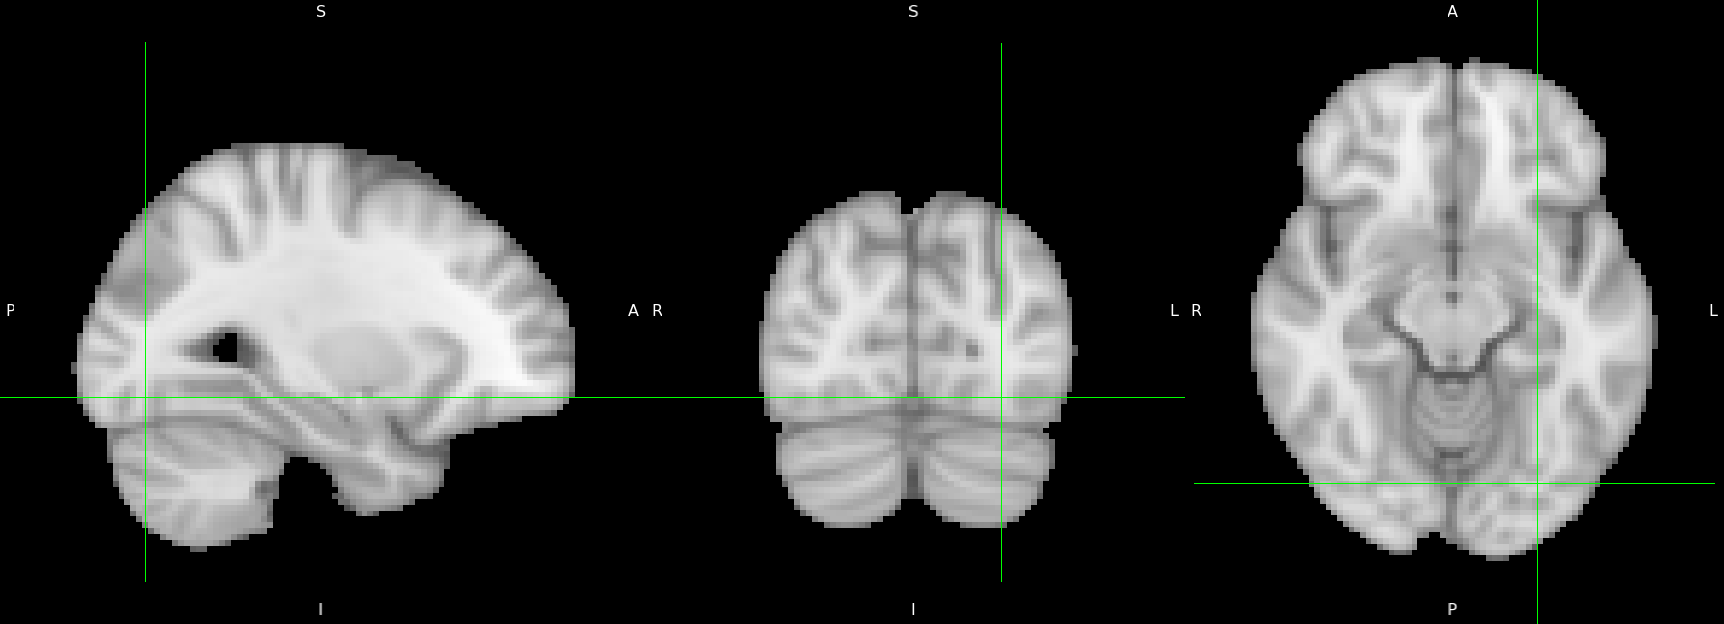

We implement the three methodologies on the data collected by Smeets et al. (2013) (openneuro accession number: ds000157). Throughout this work, we refer to this as the food data. Thirty healthy women performed a passive viewing task with blocks of food and nonfood images. Smeets et al. (2013) elucidated that food cues not only evoke hedonic brain responses; in successful self-regulators they also trigger alarm bell responses, which may reflect the neural processes underlying successful self-control.

The activation detection power by AdaFilter is quite low, as also seen in the simulation studies.

We observe from Figures 7 and 8 that in all the three dimensions, our proposal has better activation detection power than Benjamini et al. (2009): this discovers morenumber of voxels for very high values of . On the whole set of voxels, our proposal makes on average .56 more rejections. This improvement is quite significant since most of the voxels are found to be inactive in most individuals.

The portion of voxels in which Benjamini et al. (2009) and our proposal have different number of rejections is .187. The portion of hypotheses in which our proposal works better than in this set is .7. Also, in the set of voxels for which these two methods have different number of rejections, our proposal makes on average approximately 3 more rejections.

Smeets et al. (2013) mention that it is well established in the literature that foods elicited elevated (visual) attention. A meta-analysis by van der Laan et al. (2011) also showed that food images elicit stronger activation in visual areas than non-food images, which was attributed to the higher salience of foods. Indeed, we observe using Talairach coordinates that the visual cortex has significant activation with respect to the aforementioned task. Dougherty et al. (2003) estimated that the representation of the central 2 deg of visual field in areas V1, V2, V3 and hV4 is centered on the lateral-ventral aspect of the occipital lobes at Talairach coordinates (-29, -78, -11) and (25, -80, -9) (those coordinates are indicated in 9 . It is mention-worthy that our proposal detects the regions in the visual cortex with higher power than Benjamini et al. (2009).